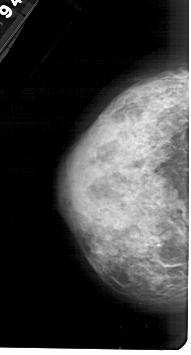

LEFT_CC LINES 4966 PIXELS_PER_LINE 2671 BITS_PER_PIXEL 12 RESOLUTION 43.5 NON_OVERLAY